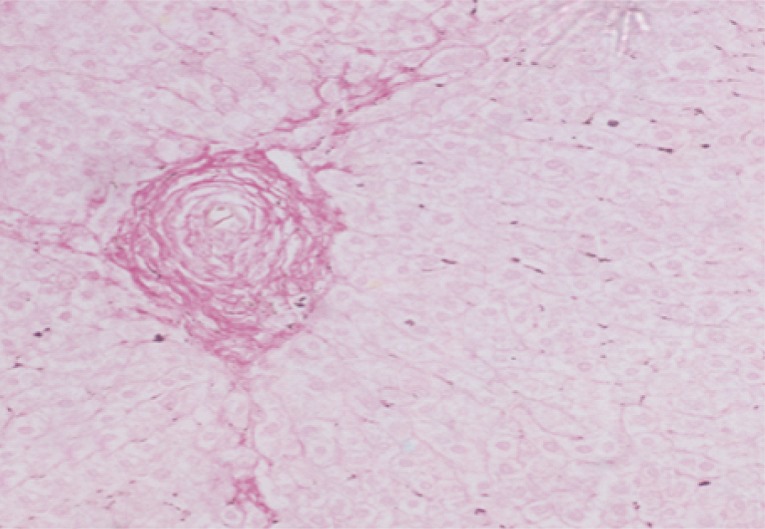

The mean granuloma count in the treated groups with BMSCs and BMSCs-HGF revealed a marked reduction accompanied by an obvious reduction in the mean granuloma number and diameter (Table 1; Figs. 2, 3).

Morphometric studies using Sirius red staining showed significant decreases in the fibrous tissue in BMSCs and BMSCs-HGF-treated groups compared to the infected control group (Figs. 6,7,8,9,10,11,12,13,14,15).

After treatment with BMSCs alone or in combination with HGF, there was an improvement in the histopathological picture of the liver which included diminution in the number and diameter of granulomas and reduction in the fibrotic content. Similar to the present findings, Abdel Aziz et al. [13] focused on the antifibrotic effect of mesenchymal stem cells (MSCs) on the liver of S. mansoni-infected mice. In their model, once granulomas were formed around the S. mansoni ova, the rate of spontaneous change of the collagen content of the granuloma was low, thereby providing a relatively stable in vivo model for analyzing collagen turnover. The histopathological examination of the liver of the S. mansoni-infected mice showed characteristic granulomas, which were cellular and contained thick collagen bands. After MSCs infusion, the granulomas decreased in size and number and became less cellular, although the concentric fibrous bands were still discernible.

In our study, the extent of fibrosis was estimated by the quantitative morphometric analysis of the collagen content in Sirius red stained liver sections. The results revealed significant decreases in the collagen content after treatment with BMSCs alone or in combination with HGF. In this regard, Ghanem et al. [8] demonstrated that fibrosis developed during the chronic phase of granulomatous inflammation in murine schistosomiasis and it represented a protective function during infection by neutralization and sequencing egg antigens that can potentially damage host tissues. The inhibitory effect of inoculated BMSCs on the collagen deposition may be related to an enhancement of fibrotic degradation rather than a decrease in fibrosis synthesis.